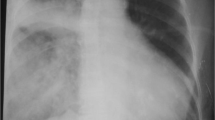

Routine laboratory analyses were normal except for hypalbuminemia (8 g/L, normal range 35–52 g/L), elevated B-natriuretic peptide (BNP; 844 ng/L, normal value < 177 ng/L), and C-reactive protein (CRP; 40 mg/L, normal value < 10 mg/L). Arterial blood gas analysis (BGA) confirmed hypoxemia: partial pressure of oxygen in arterial blood (PaO2) of 8 kPa. A computed tomography (CT) scan of her chest revealed bilateral central pulmonary embolism and ground glass opacities (Fig. 1a) [3]. Echocardiography showed dilatation of her right ventricle with normal right ventricular function, while her left ventricle showed systolic D-shaping with normal systolic function [4]. Systolic pulmonary artery pressure (PAP) was estimated at 54 mmHg. Transpulmonary thermodilution and pulse contour cardiac output (Pulsion Medical Systems©) displayed a normal cardiac index (4 L/minute per m2), a slightly increased extravascular lung water index (10 ml/kg, normal range 3–7 ml/kg), and a central venous pressure of 17 mmHg. Because of worsening gas exchange over 3 days on non-invasive ventilation (NIV), a repeat CT scan was performed and profound ground glass opacities (Fig. 1b) were noted. Bronchoalveolar lavage (BAL) remained sterile.